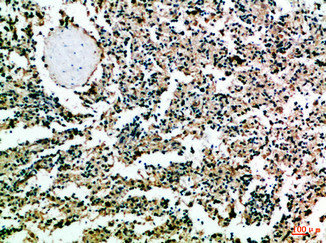

Immunohistochemical analysis of paraffin-embedded Human-tonsil, antibody was diluted at 1:100

Immunohistochemical analysis of paraffin-embedded Human-spleen, antibody was diluted at 1:100